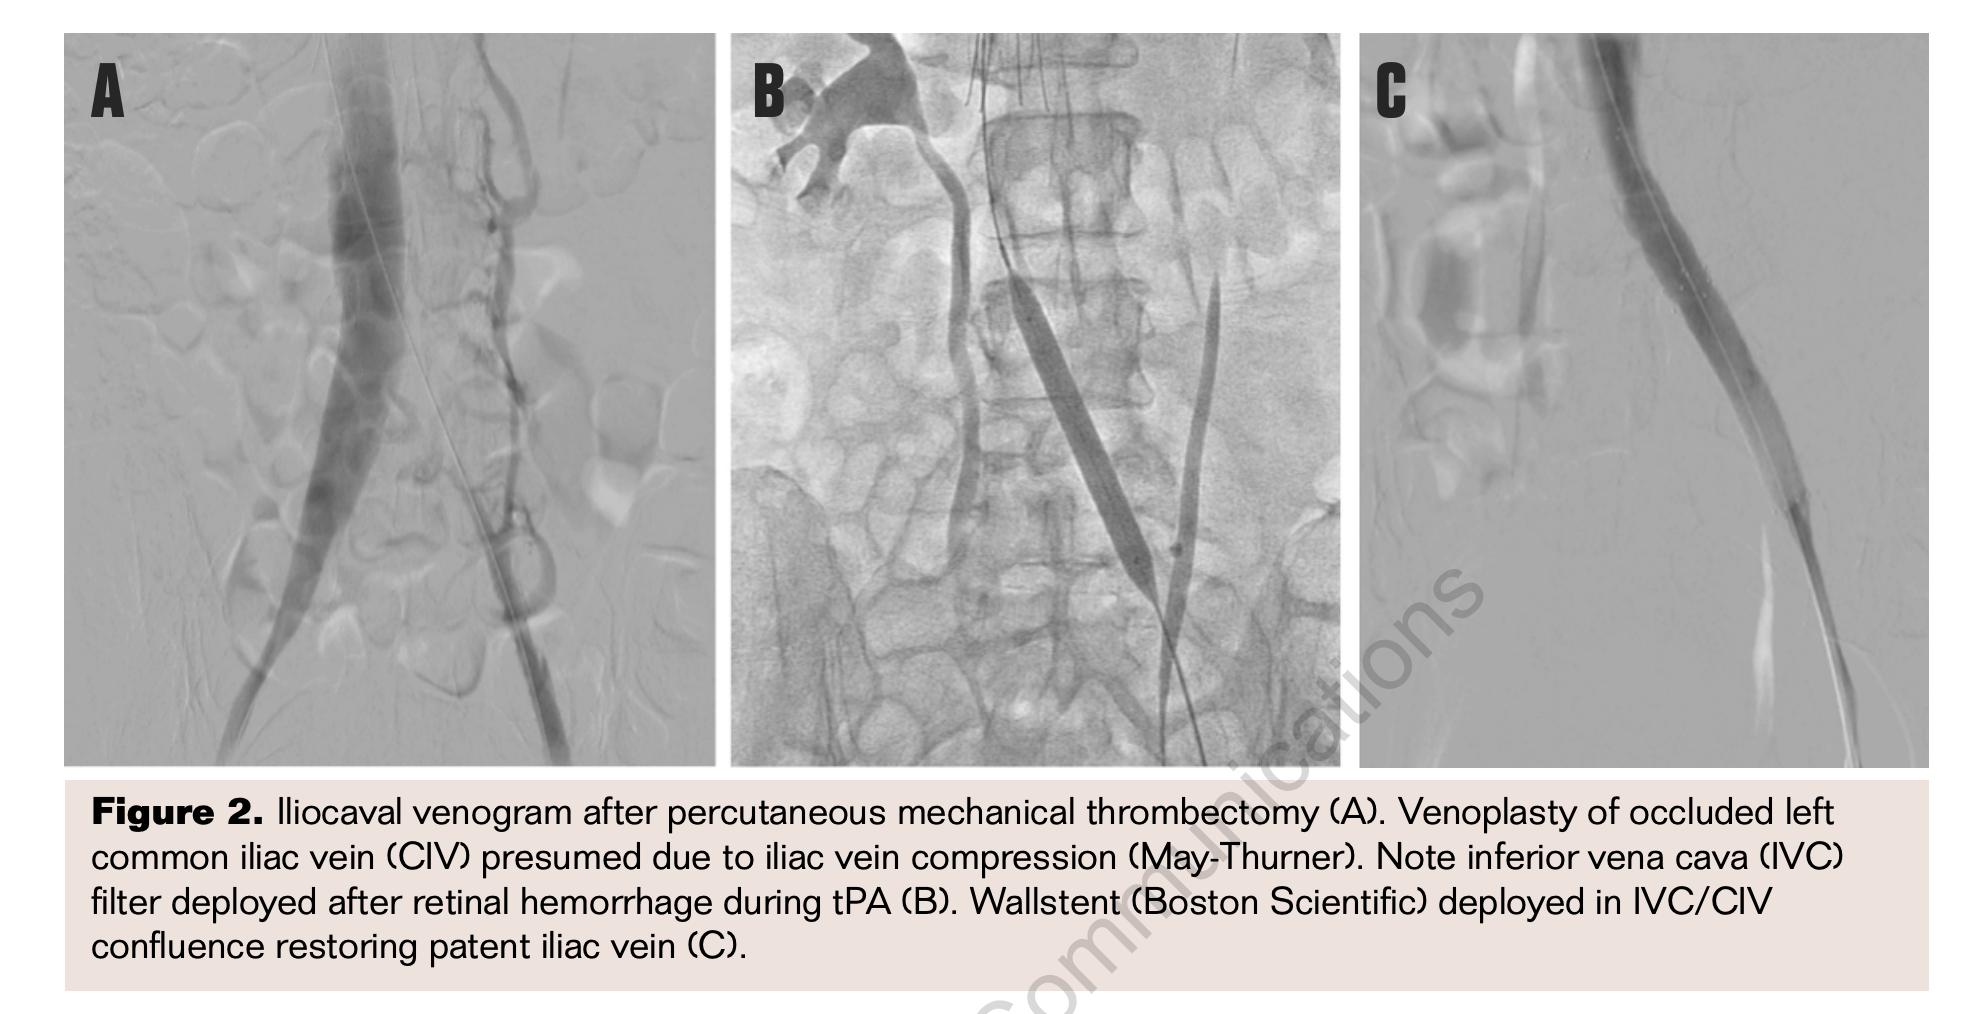

Once the occluded iliac vein is rendered patent by the modalities described above, in cases of suspected iliac vein compression, contrast venography with adjunctive IVUS are complementary tools to confirm the diagnosis and guide therapy (Figure 2). It is “de rigeur” to perform balloon venoplasty of the underlying outflow obstruction followed by stenting of the segment in order to ensure long-term success. These measures not only prevent early venous reocclusion but also improve primary patency rates to 70% to 80% in the first year following treatment. The degree of lysis also has been found to be a major predictor of early and long-term patency. More complete clearance of thrombus yields venous patency rates in excess of 75% in most studies, whereas incomplete lysis (>50% remaining residual clot) leads to poor (<40%) patency.15 Stenting relieves the mechanical obstruction in the common iliac vein, offers definitive immediate technical success, and improves long-term vessel patency. A large self-expanding stent (12 mm to 16 mm in diameter) is deployed across the stenosis and extended into the IVC. It is generally oversized slightly to the diameter of the common iliac vein, and is allowed to “mushroom” up into the IVC, just above the iliocaval junction, so that anchoring is secure and the risk of stent migration reduced. Intravascular ultrasound can also be helpful in these instances, to size the stent appropriately to the dimensions of the vessel and to select the optimal length of stent that will allow secure anchoring at the iliocaval junction. Intravascular ultrasound can also delineate the adequacy of a balloon percutaneous transluminal angioplasty result, quantify the presence of residual thrombus within the treated segment of vein with greater clarity than venography, and help assess the need for further thrombus removal. Once the outflow obstruction is treated, thrombolysis may be continued for an additional 24 to 48 hours for optimal clot resolution. In some studies of acute DVT with underlying MTS, primary 2-year stent patency rates for primary and secondary iliac vein compression approach 95% to 100%.21,22